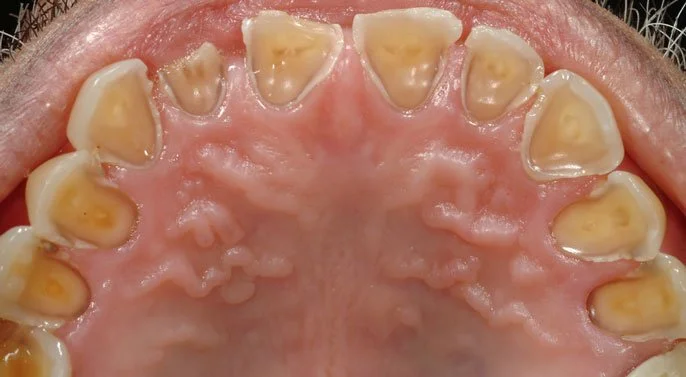

When stomach acid repeatedly enters the mouth, it can wear away the protective enamel on your teeth. This can lead to:

Tooth erosion: Enamel thinning and yellowing

Yellowing or thinning enamel

Rounded or shiny edges on teeth